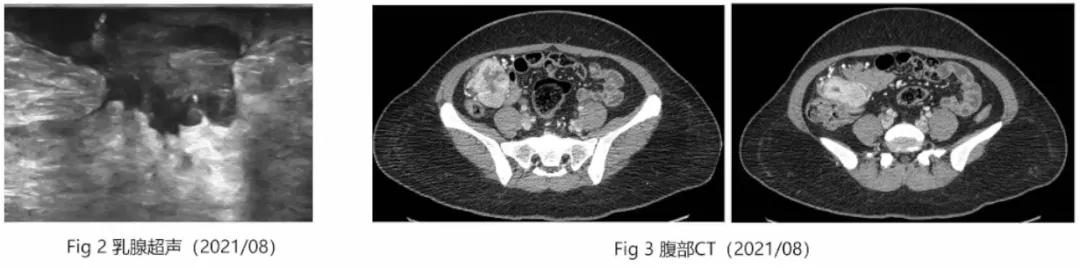

2021.8乳腺彩超示:左侧乳腺结节大小约2.0×1.9cm,乳腺结节部分缓解(Fig 2)。

CT示:右下腹部肿块(6*5cm)较前增大,考虑小肠来源胃肠间质瘤(Fig 3)。